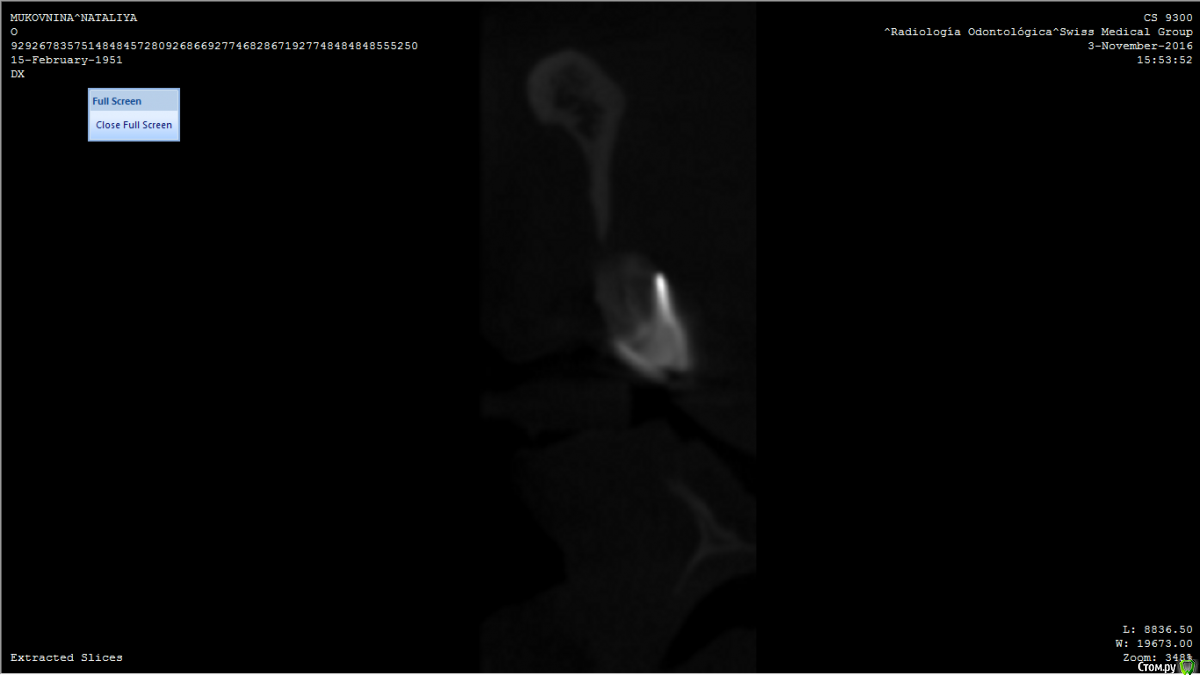

Oxi78 Опубликовано 18 декабря, 2016 Поделиться Опубликовано 18 декабря, 2016 ЗдравствуйтеЖенщина 65 лет. Полная адентия и атрофия. Подскажите пожалуйста можно ли протезировать на имплантах? ( All in 4) Кости судя по сканам не достаточно.Можно ли сделать наращивание кости? Не получается открыть все файлы компьютерной томографии.Спасибо Ссылка на комментарий

Oxi78 Опубликовано 19 декабря, 2016 Автор Поделиться Опубликовано 19 декабря, 2016 Спасибо за ответ. Сопутствующие заболевания остеопороз, аутоимунный тиреоидит в не тяжелой форме. Консультировались с эндокоинологом. Он разрешил имплантацию зубов. Никаких таблеток не принимает. Один раз в год укол от остеопороза. Общее самочуствие хорошее. Ходили на прием к имплантологу( женщина проживает в Аргентине). Врач сказал что только вставные протезы. Импланты вкручивать не куда. На верхней челюсти тоже мало кости. 1.Можно ли рассчитывать на НКР(направленную костную регенерацию)? 2.Нужно ли сделать новую компьютерную томографию? Не хотелось бы ставить простые протезы. Спасибо. Ссылка на комментарий